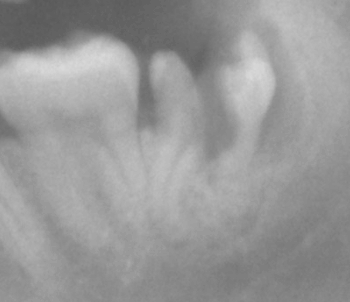

分割した左側の方は「コマ」のようにグルングルン動くのですが

「取れない」!汗!

バナナのように曲がっている方向(後ろ)に出そうとすると、頭が当たる、、、

頭を削り過ぎると、抜きたくても器具でつかみ難くなるし、、、

智恵の和じゃ! |

ブラブラ動くなかで歯の頭を削りながら調整して、、、大汗!!!

真っ直ぐだから簡単に30分以内には抜けると思っていたのですが、、、

結局1時間もかかってしまいました!汗!

すみませんでした! |